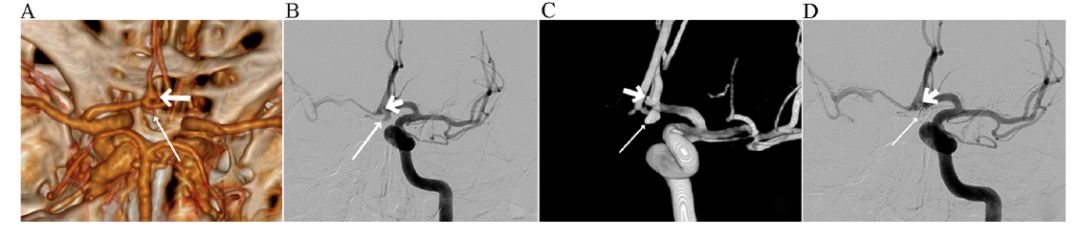

图4. 44岁女性患者。“左MCA的初始段的小动脉瘤(短箭头)”在常规VR图像(A)和立体VR图像上均为假阳性发现。DSA图像(B)证实,A图上的“左MCA的初始段的小动脉瘤”是MCA小分支起始部(短箭头)。1枚右PcoA动脉瘤,在常规VR图像、DSA图像(C)和3DRA图像(D)上均清楚地显示(长箭头)。